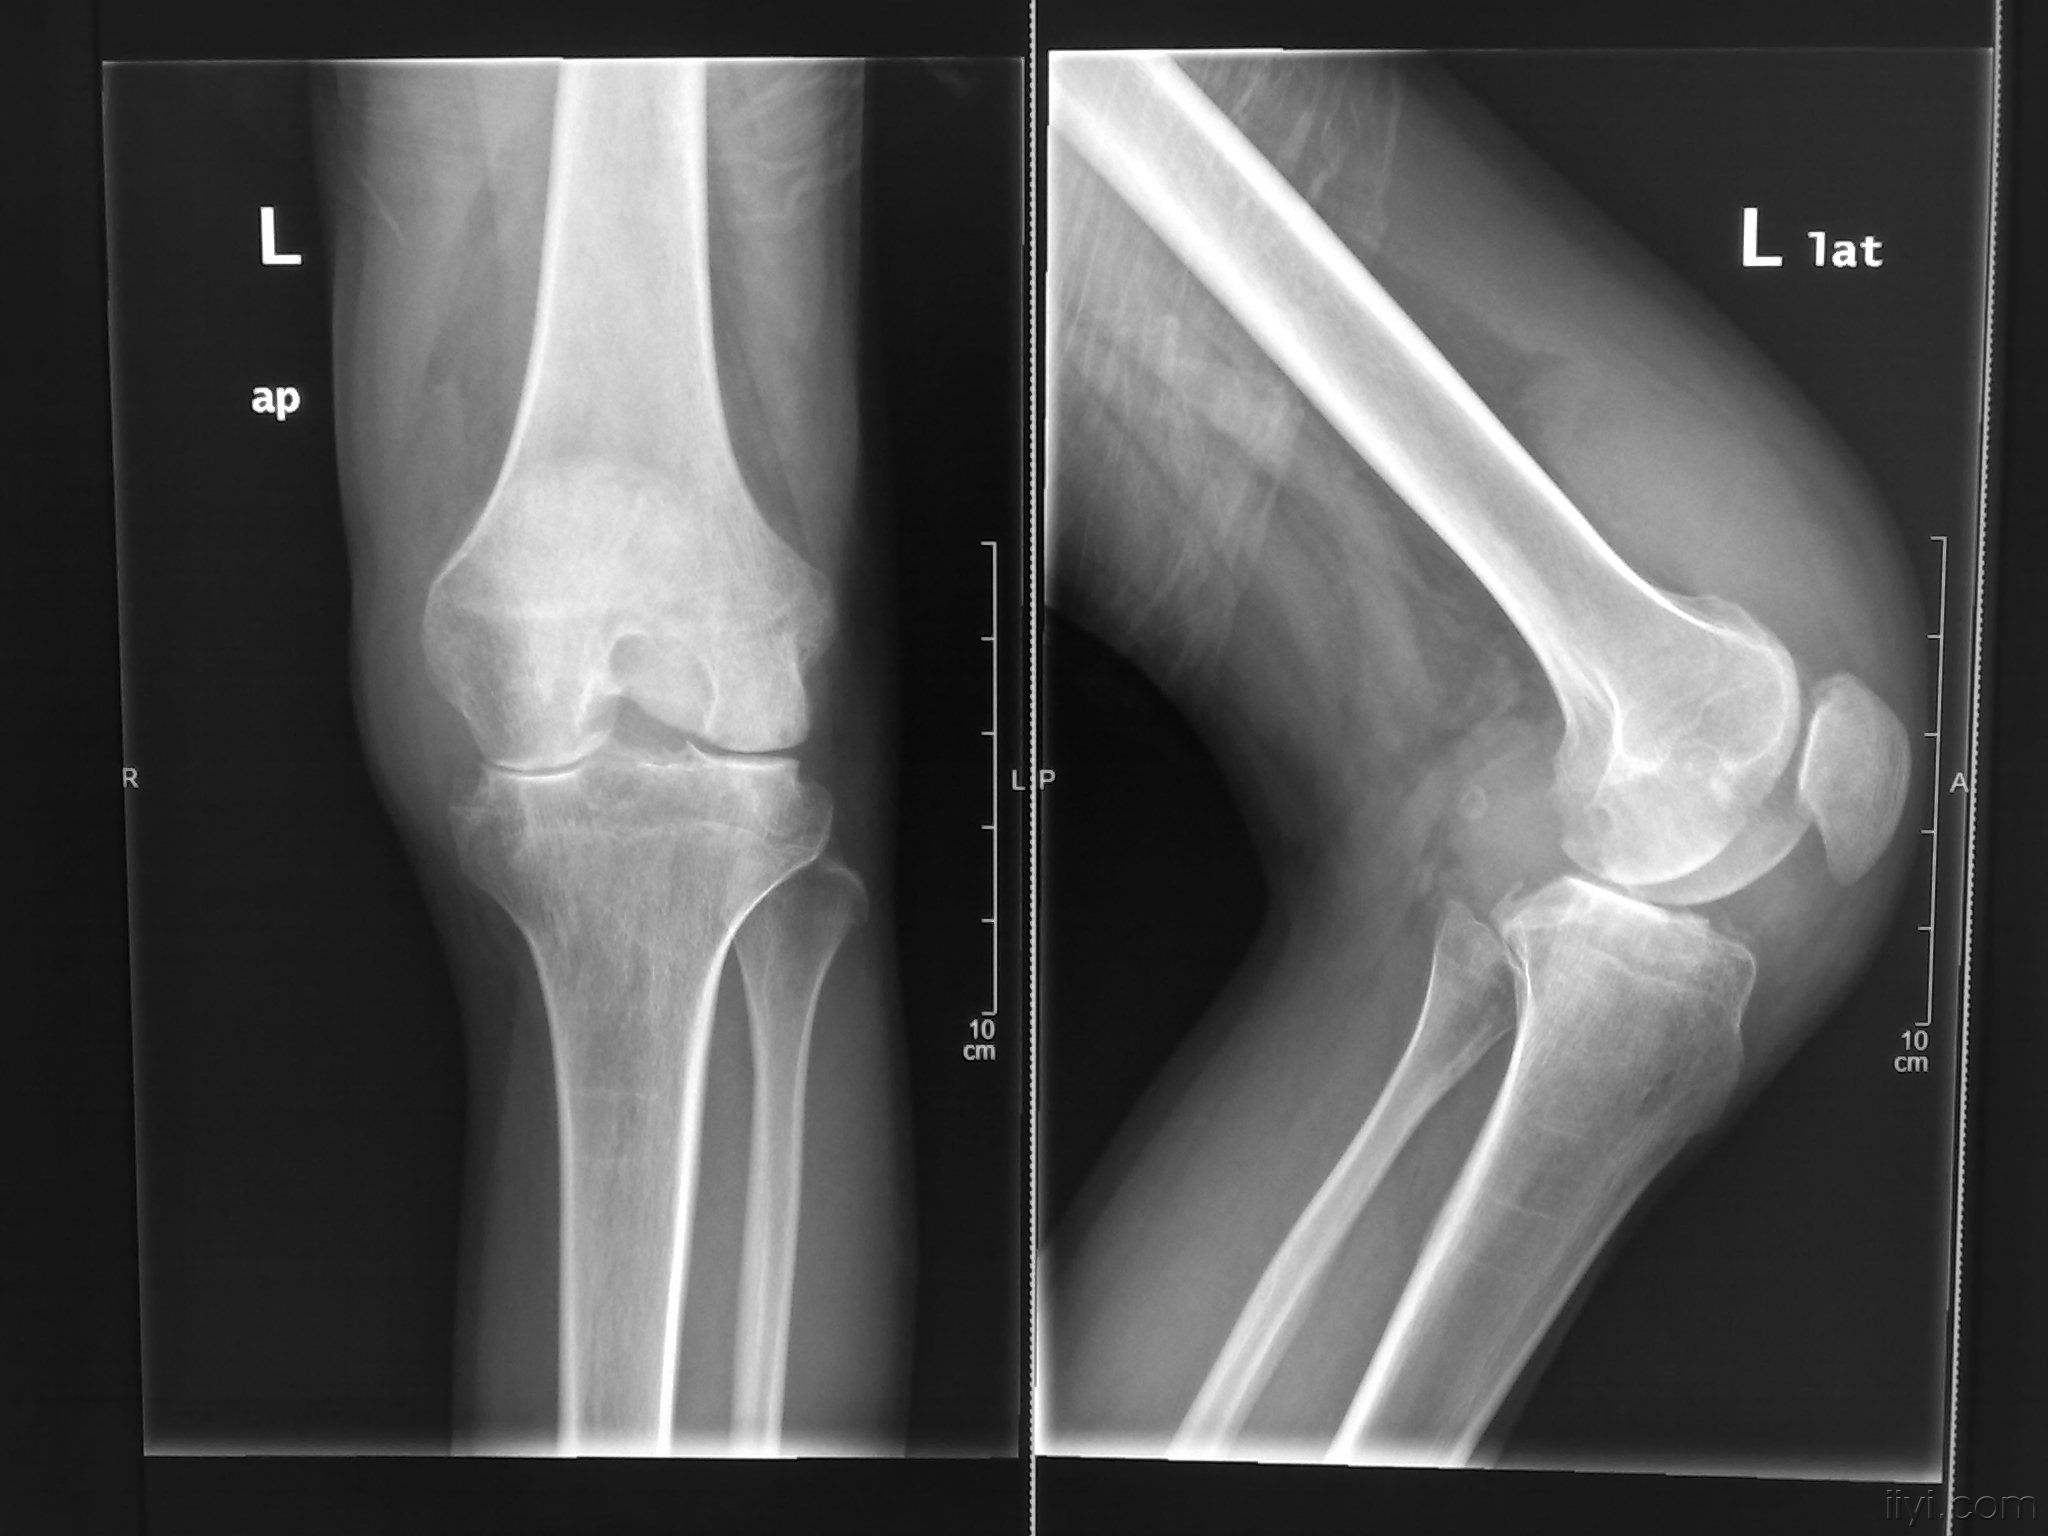

类风湿在临床上指的一般就是类风湿性关节炎,这是一种病因不 ...

类风湿性关节炎的治疗非常的困难,在治疗的时候主要的目的是 ...

在生活中,人们对类风湿性关节炎疾病都是比较熟悉的,一些中 ...

类风湿好发于中老年女性,尤其是女性发病率高于男性,一旦患 ...